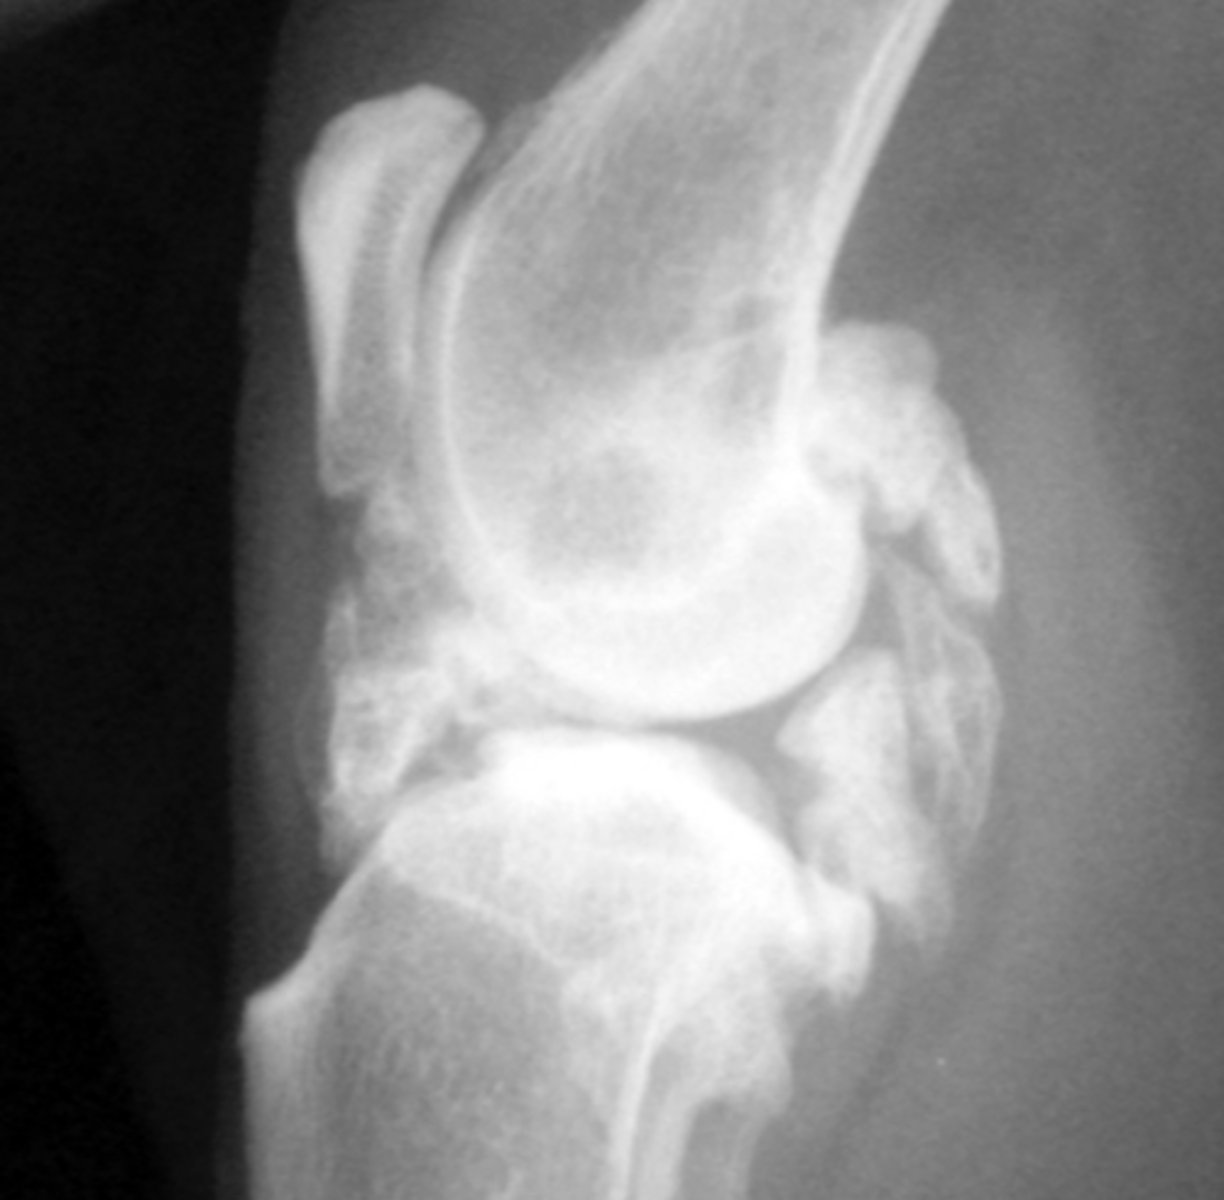

Osteophyte

Identify the pathology?

Enthesiophyte

Inside the joint - periarticular margin

Where would you find an osteophyte?

Outside joint capsule

Where would you find an enthesiophyte?